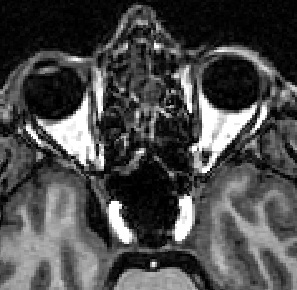

zoom_chiasma